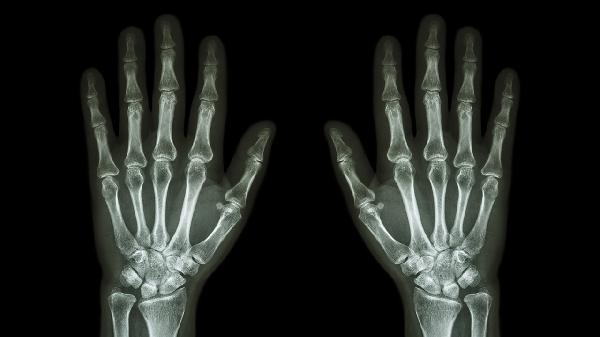

外力撞击或扭伤可能导致右手小指关节周围软组织损伤,表现为局部肿胀、疼痛、活动受限。轻微外伤可通过冰敷减轻肿胀,48小时后热敷促进血液循环。若出现持续疼痛或关节畸形,需排除骨折可能,建议及时就医拍摄X线片。遵医嘱可使用双氯芬酸钠缓释片、云南白药气雾剂等药物缓解症状。